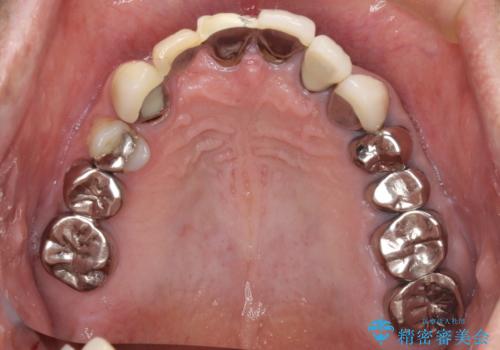

- 前歯のブリッジのセラミックが欠けてしまい、作り直したいとのことで来院された患者様です。

犬歯はブリッジの中で虫歯が進行していたため、根管治療からやり直しをした後、オールセラミックブリッジにて補綴することとしました。